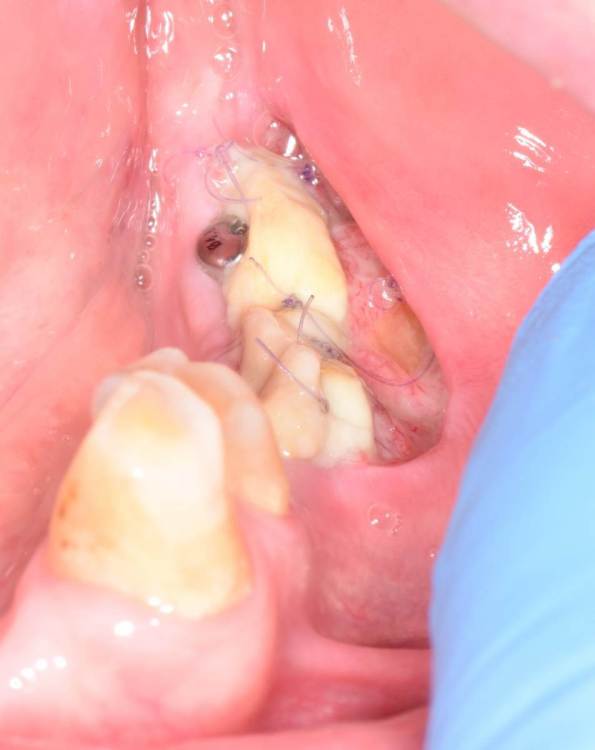

Fin Опубликовано 23 июня, 2023 Поделиться Опубликовано 23 июня, 2023 Коллеги. Подскажите какая самая частая проблема некроза СДТ. Уже много всего перепробовал. На 7 день вижу некроз. Раньше думал что очень много шью, и передавливаю. Потом думал что транспоантат очень толстый и сосуды не прорастают, но истончение СДТ не дало результата. На прошлой неделе пришил слабо, но все равно получил некроз.Вот не могу понять где проблема. Ссылка на комментарий

АнтонТЛТ Опубликовано 23 июня, 2023 Поделиться Опубликовано 23 июня, 2023 Есть фото принимающего ложа? Часть трансплантата висит в воздухе Ссылка на комментарий

АнтонТЛТ Опубликовано 23 июня, 2023 Поделиться Опубликовано 23 июня, 2023 А вообще сдт должен лежать плотно на принимающем ложе и быть неподвижным если его тыркать из стороны в сторону. 1 1 Ссылка на комментарий

Fin Опубликовано 23 июня, 2023 Поделиться Опубликовано 23 июня, 2023 29 минут назад, АнтонТЛТ сказал: Есть фото принимающего ложа? Часть трансплантата висит в воздухе В воздухе была только часть которая упиралась в ФДМ. В остальных местах на кости.Фото к сожалению нет, первые фото с новым фотоаппаратом, не разобрался ещё. 26 минут назад, АнтонТЛТ сказал: А вообще сдт должен лежать плотно на принимающем ложе и быть неподвижным если его тыркать из стороны в сторону. Да, понимаю о чем вы, как раз так и стараюсь делать, проверяю.Имею большое желание попробовать пинами фиксировать. Ссылка на комментарий